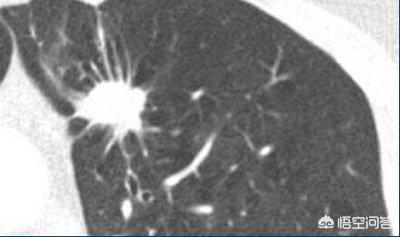

Knoten mit offensichtlichen Anzeichen von Bösartigkeit, wie z. B. lobulierte Knoten mit Graten und Blutgefäßen, werden für einen aggressiven Eingriff, in der Regel eine Biopsie oder eine Operation, empfohlen.

Eine Nachuntersuchung wird in der Regel für Knoten empfohlen, die keine Anzeichen von Bösartigkeit aufweisen, einschließlich gutartiger Knoten und potenziell bösartiger Knoten. Gutartige Knoten können resorbiert werden oder während der Nachuntersuchung unverändert bleiben, aber potenziell bösartige Knoten können sich allmählich offenbaren und werden genauso behandelt wie bösartige Knoten.